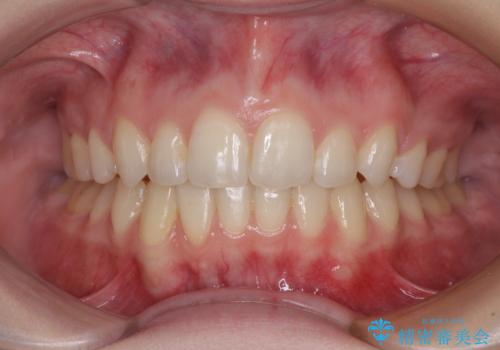

下顎の骨格的なズレが大きかったため、上下歯列のバランスが取れるか心配でしたが、上下ともに左右対称に近い歯列で治療を終えることができました。